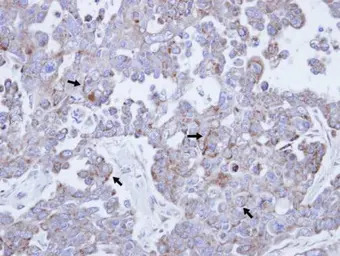

Immunohistochemical analysis of paraffin-embedded OVCAR3 xenograft, using IL3RB (GTX113659) antibody at 1:100 dilution.

Antigen Retrieval: Trilogy™ (EDTA based, pH 8.0) buffer, 15min